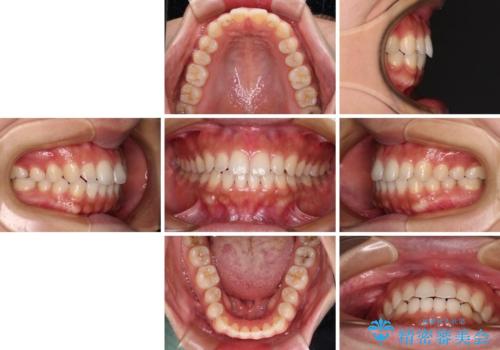

インビザラインを用いた上顎の部分矯正

- 上顎前歯の叢生を気にして来院された患者様です。

下顎前歯や上下奥歯の咬み合わせには殆ど問題がないため、上顎前歯のみを矯正する治療を提案しました。

ワイヤー装置でもインビザラインでも可能でしたが、前歯のみをきれいに排列するのであればインビザラインの方が仕上がりが良いので、インビザライン・ライトにて治療を行うこととしました。